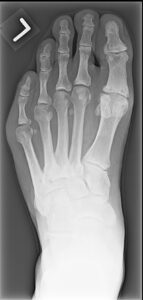

FIGURES 1: Midfoot osteophytes and joint space narrowing in left foot of 56-year-old male. (Click to enlarge.)

Midfoot osteoarthritis (OA) is a subtype of foot OA in which OA exists in one or more joints of the midfoot, most often the tarsometatarsal, talonavicular or naviculocuneiform joints (see Figure 1). OA in this region is relatively under-recognized but is a key contributor to foot pain and disability, especially in middle-to-older-aged adults.